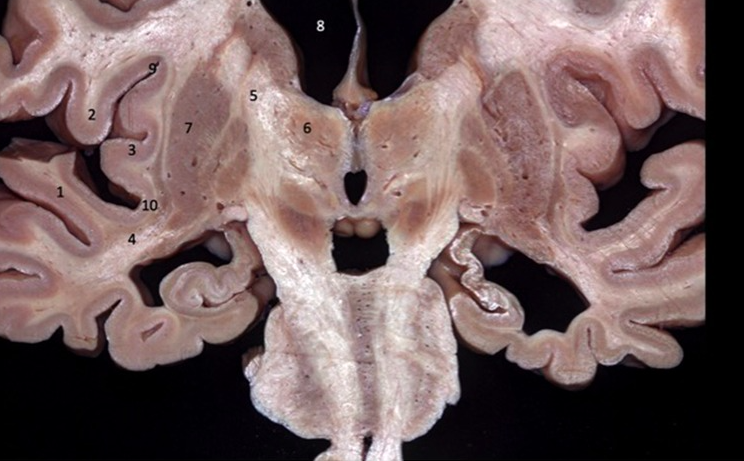

Label 5, 6 & 7

1 - superior temporal gyrus;

2 - inferior frontal gyrus; 3 - insular cortex;

4 - temporal stem;

5 - internal capsule;

6 - thalamus;

7 - lentiform nucleus (the internal and external globus pallidus and the putamen)

8 - frontal horn;

9 - superior circular sulcus;

10 - inferior circular sulcus.

1 - superior temporal gyrus; 2 - inferior frontal gyrus; 3 - insular cortex; 4 - temporal stem; **5 - internal capsule;** **6 - thalamus;** **7 - lentiform nucleus** (the internal and external globus pallidus and the putamen) 8 - frontal horn; 9 - superior circular sulcus; 10 - inferior circular sulcus.